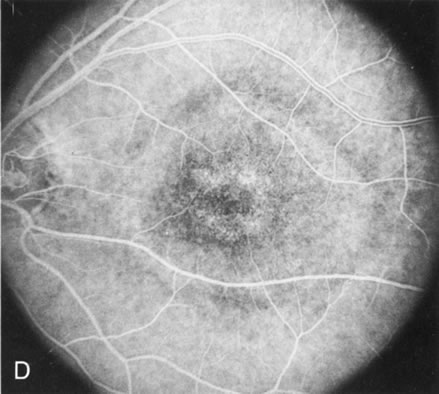

Of more clinical importance is the role of FA in the diagnosis and treatment of cystoid macular edema (CME) (Fig. 1C and D). Stereoscopic FA indicates that the leakage, which may be diffuse or have the typical petaloid stellate appearance of CME, can come from the perifoveal retinal capillaries, from the choroid through the RPE, or from a combination of both sources.4 With the recent suggestion that CME in RP may be successfully treated with acetazolamide,5, 6 FA is thus important to document the diagnosis of CME, establish the origin(s) of leakage, and follow patients during and after therapy.